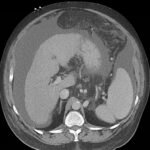

Endovascular coil embolization continues to become a more frequent modality of addressing hemorrhage and bleeding in patients. Migration refers to the coil unraveling or moving from the original embolization site. Migration of a coil is a known complication which can lead to serious consequences based on where the coil migrates. Despite increasing efforts to improve safety and technique, the risk of migration remains. We present a case of an embolization coil that migrated to the right ventricle, which was incidentally found roughly 2 months after undergoing an interventional radiology procedure for gastric variceal bleeding. The patient presented to the emergency department with dyspnea and abdominal pain. Unique images were obtained during his visit and in subsequent follow-up. As use of vascular embolization coils continues to become more commonplace, understanding the risks and complications of these procedures remains an important aspect of providing care for patients once they have left the interventional radiology suite. Coil migration should be a differential to consider in patients who present to the emergency department with signs or symptoms of arrhythmia or pulmonary embolism who have undergone a coil embolization procedure.